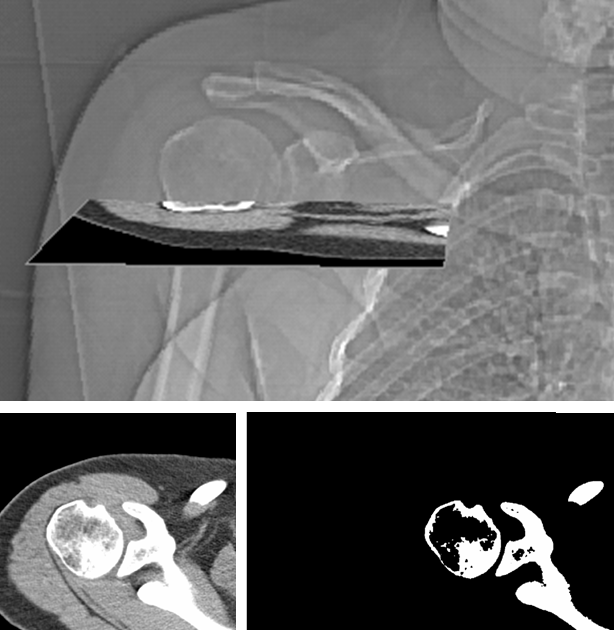

From musculoskeletalkey.com

2 The Shoulder Diagnostic Imaging Musculoskeletal Key What Is Another Name For A Bicipital Groove The bicipital groove (bg), a bony sulcus between the greater and lesser tubercles of the proximal humerus, allows for the smooth. The tendon of the long. It is sometimes referred to as the bicipital groove. The intertubercular sulcus is an indentation located between the two tubercles. The meaning of bicipital groove is a furrow on the upper part of the. What Is Another Name For A Bicipital Groove.

From 123sonography.com

What can you find in the short axis view of the biceps tendon on the What Is Another Name For A Bicipital Groove The intertubercular sulcus, also known as the intertubercular groove, or bicipital groove, is a groove separating the greater and lesser tubercles of the humerus. The long tendon of the biceps brachii and an. It is sometimes referred to as the bicipital groove. The intertubercular sulcus is an indentation located between the two tubercles. The intertubercular sulcus (intertubercular groove or bicipital. What Is Another Name For A Bicipital Groove.